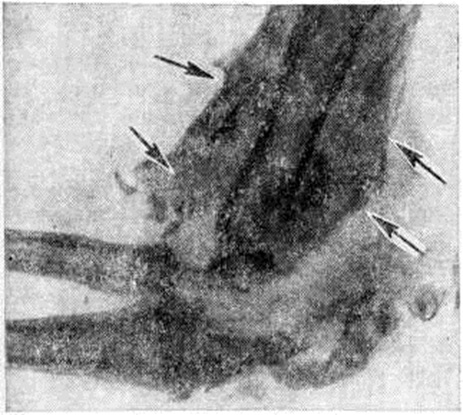

Патологическая анатомия. При макроскопическом исследовании спинного мозга обнаруживаются утолщение твёрдой и паутинной оболочек, сращения их на отдельных участках между собой и с мягкой оболочкой, уплощение, утолщение или истончение отдельных или всех его сегментов. В некоторых расширенных сегментах спинного мозга определяются также уплотнения и флюктуация. Характерные для Сирингомиелия единичные или множественные патологический полости (рисунок 1) локализуются преимущественно в центральных отделах сегментов спинного мозга, иногда и в мозговом стволе; белая спайка при этом, как правило, сохранена. Полости в большинстве случаев не связаны с центральным каналом, распространяются на задние столбы и центральные отделы задних канатиков; встречаются они и в переднем канатике. Конфигурация их разнообразна: круглая, овальная, щелевидная, в форме песочных часов, с одним или несколькими дивертикулами. Размеры полостей также различны: от узких, обнаруживаемых только при надавливании на боковые, переднюю или заднюю поверхности спинного мозга, до крупных, занимающих почти весь поперечник сегмента. Патологический полости могут быть настолько велики, что спинной мозг приобретает форму тонкостенной трубки и легко рвётся при неосторожном выделении его из твёрдой оболочки. Чаще всего полости распространяются на 1—2, реже — на большее число сегментов. Описано наблюдение, в котором полости простирались от сегмента СIII до LII. В единичных случаях полости достигают продолговатого мозга и варолиева моста (моста головного мозга. Варолиев мост, как правило, является границей распространения их в оральном направлении, однако известно наблюдение, когда щелевидная полость простиралась от крестцовых сегментов через все отделы спинного мозга, продолговатый мозг, правую половину варолиева моста, правую ножку мозга, внутреннюю капсулу, хвостатое ядро и заканчивалось у переднего рога бокового желудочка мозга.

Рис. 1. | ||